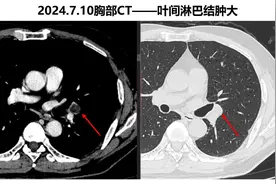

对于刚发现的直径比较小的肺磨玻璃结节,观察一段时间,看看它的变化,再决定是不是手术,是绝对安全的。有一位家住天津55岁的女士,偶然的原因拍胸部CT,发现了肺部有两个磨玻璃结节,她带着片子过来找我看,我看到这两个结节都比较靠近外周,大的那个有6毫米,看起来恶性的可能性比较大,但直径比较小,可以再观察一下。